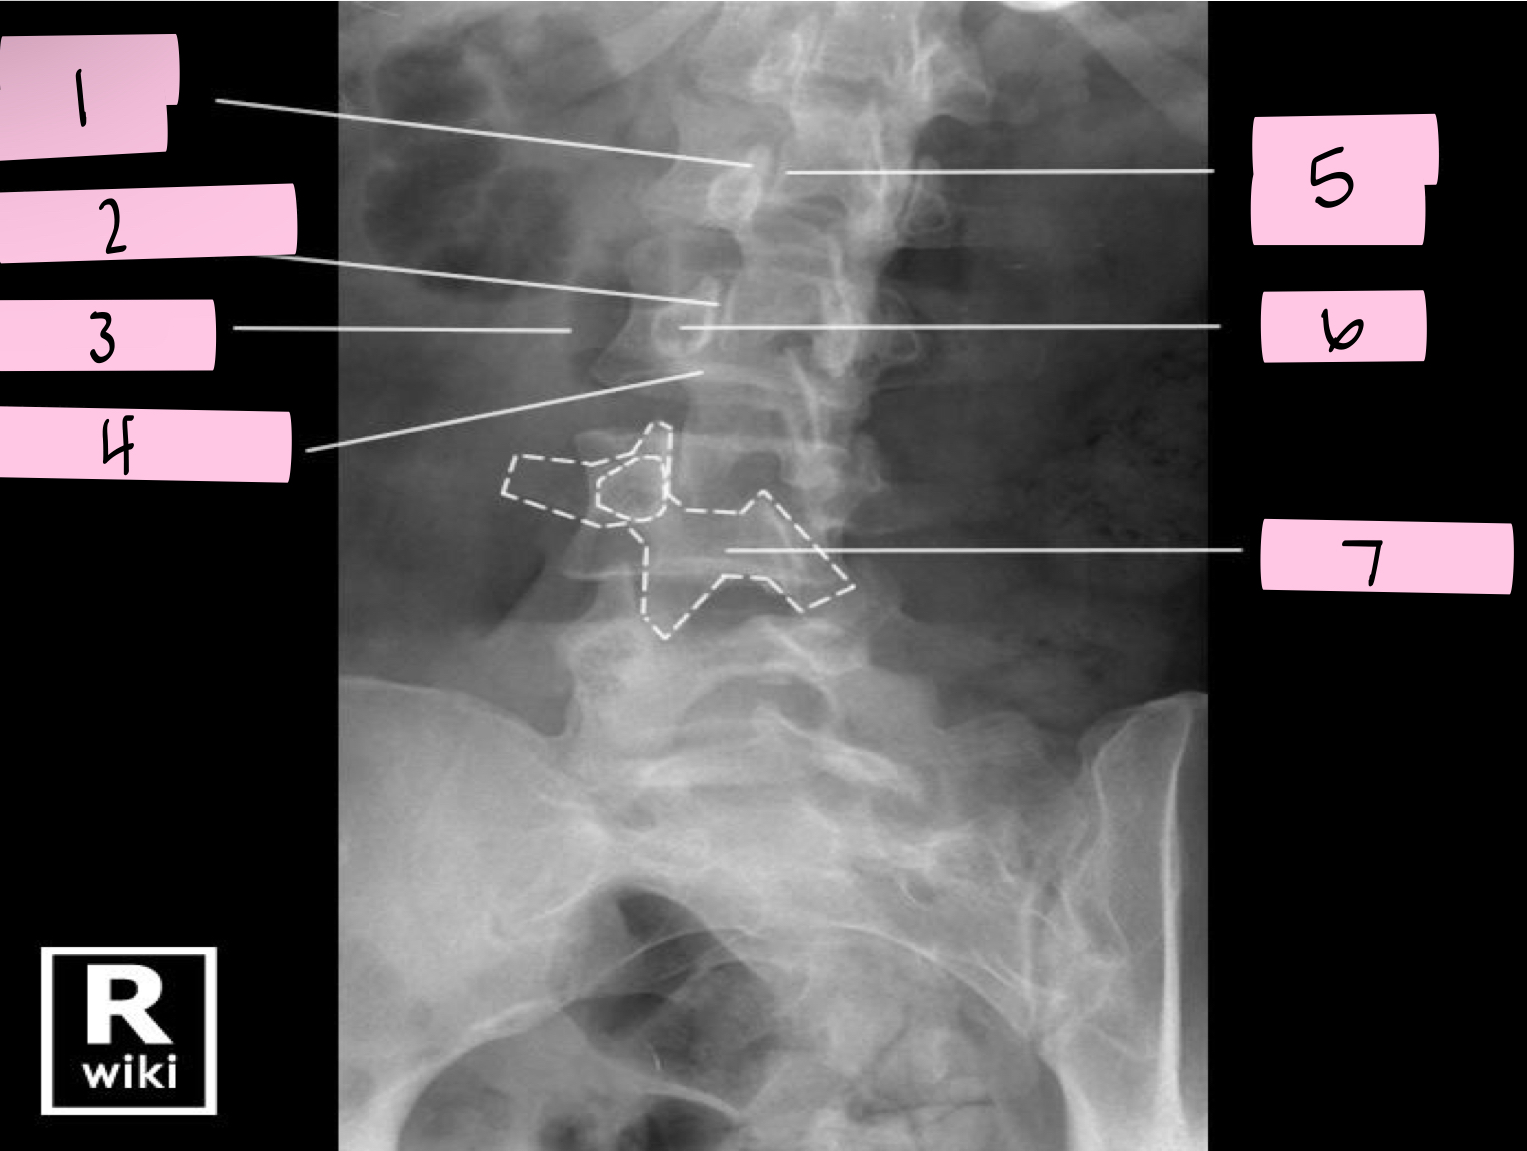

What is 1 pointing to?

Superior articular process

What is 2 pointing to?

Zygapophyseal joint

What is 3 pointing to?

Transverse process

What is 4 pointing to?

Pars interarticularis

What is 5 pointing to?

Inferior articular process

What is 6 pointing to?

Pedicle

What is 7 pointing to?

Scotty dog